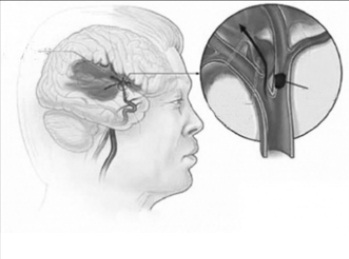

Đột quỵ xảy ra do cục máu đông làm nghẽn lòng động mạch làm thiếu máu não hoặc gây chảy máu trong não. Việc điều trị ban đầu đối với đột quỵ bao gồm dùng thuốc để phá vỡ cục máu đông, ngăn chặn thiệt hại thêm cho não và phục hồi các chức năng não.

Giảm nguy cơ đột quỵ tái phát: Một bệnh nhân đã bị đột quỵ có nguy cơ bị đột quỵ tái phát, nếu không được điều trị thích hợp và thiếu kiểm soát. Để giảm nguy cơ này cần đảm bảo bệnh nhân dùng thuốc đúng cách, thực hiện đúng các bài tập phục hồi và tham khảo ý kiến bác sĩ thường xuyên.Cục máu đông làm nghẽn lòng động mạch gây nhồi máu não.

Cục máu đông làm nghẽn lòng động mạch gây nhồi máu não.

Cục máu đông làm nghẽn lòng động mạch gây nhồi máu não.